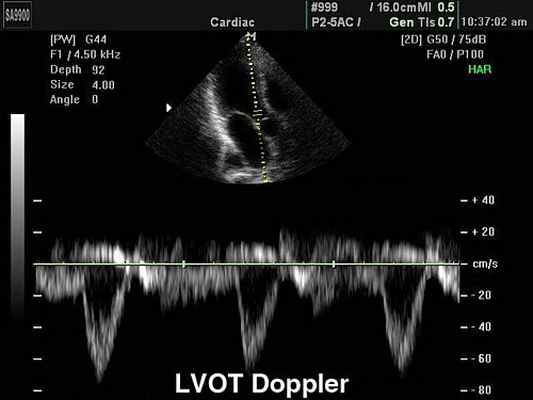

ЭхоКГ способна определить направление кровотока, измерить скорость движения крови и сердечной стенки, если она дополняется эффектом Доплера. Одним из недостатков эхокардиографии с допплеровским анализом является то, что для получения точных результатов ультразвуковой луч и поток крови должны быть максимально параллельны, что ограничивает возможность исследовать некоторые отделы сердца.

Измерение скоростных характеристик позволяет оценить:

Допплерэхокардиография позволяет измерить все вышеперечисленные параметры, которые очень важны при оценке детской сердечной патологии (врожденные пороки) без использования инвазивной процедуры — катетеризации сердца. Помимо этого, назначение эхокардиографии с допплеровским анализом ребенку не несет никакой угрозы по сравнению с компьютерной томографией, где используется рентгеновское излучение.